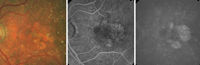

La angiografía con verde de indocianina es más útil que la AGF en estos casos, ya que permite delimitar los pólipos coroideos con mucha precisión (

Figura 19).

Figura 19. Retinografía (A), angiografía fluoresceínica (B) y angiografía con verde de indocianina (C) de vasculopatía coroidea polipoidea.